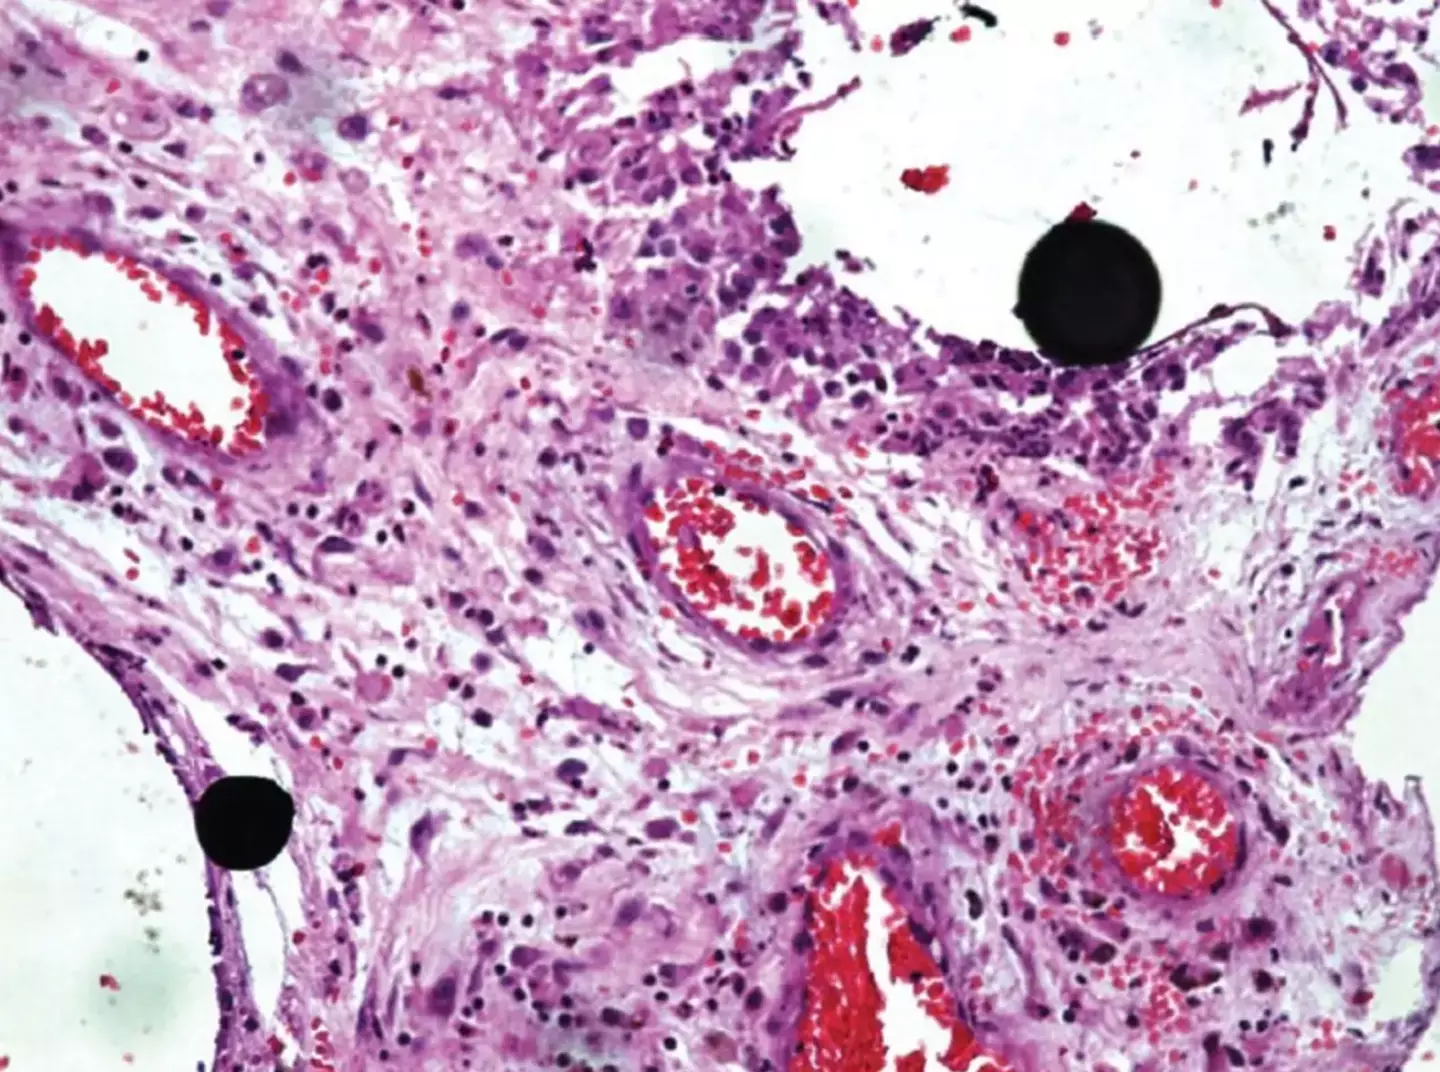

The report states: "The patient did not develop clinical signs of chronic poisoning, proving that subcutaneous mercury injection has a low risk of systemic toxicity, and that histopathology plays an important role in diagnosis."